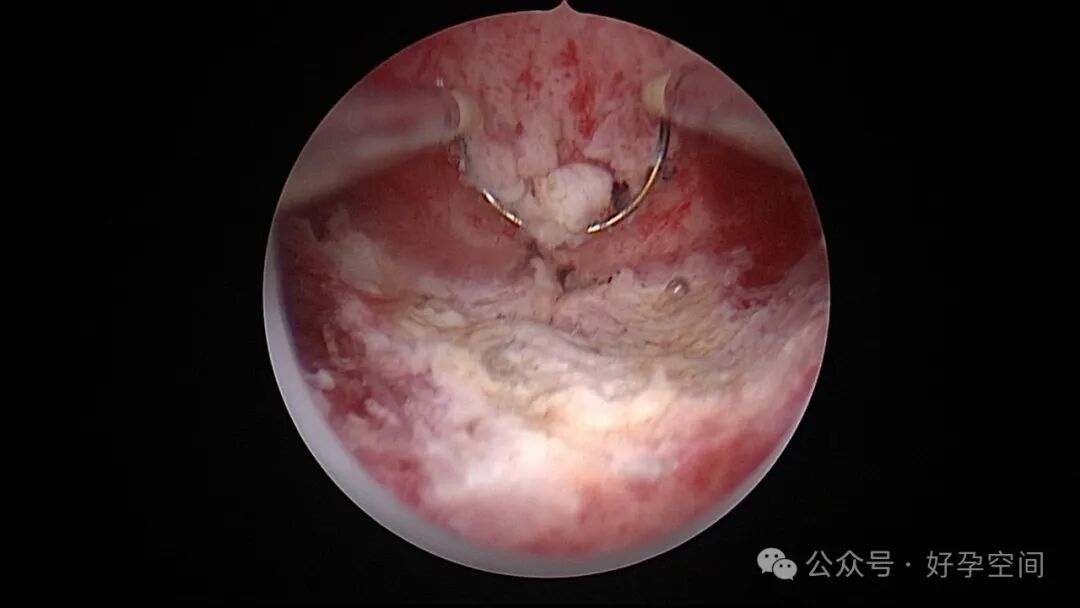

从以上病例可知,人流不全、药流不全有时候难以避免,宫内占位也并非都是胚物残留,门诊手术医生可能成为背锅侠。宫腔镜辅助下清宫可以最大限度地避免残留,及时发现宫腔内占位病变,切除送病检以明确诊断。